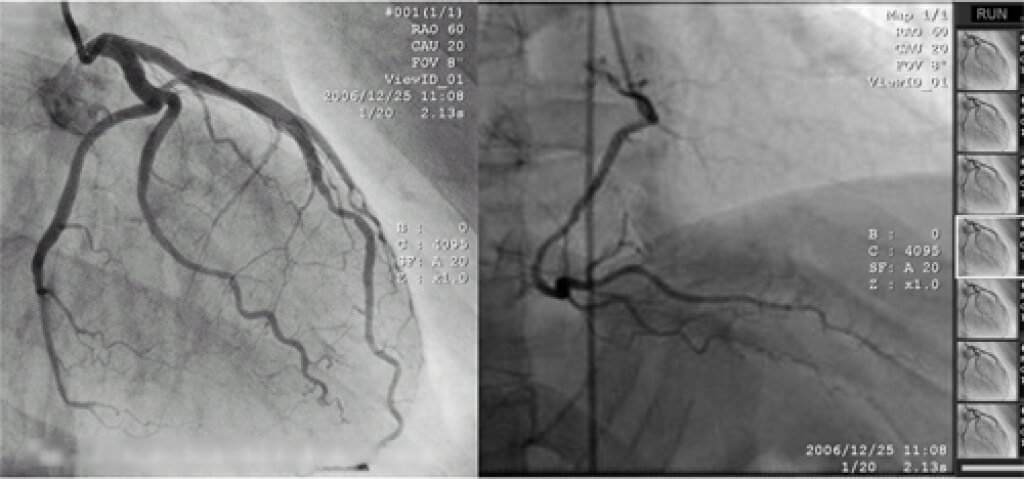

Наиболее точным методом диагностики ИБС является рентгеноконтрастное исследование (коронарография), при котором контрастное вещество вводится в венечные артерии посредством катетеров.

На основании данных, полученных в ходе исследования, решается вопрос о возможности проведении стентирования, баллонной ангиопластики или коронарного шунтирования сосудов сердца.